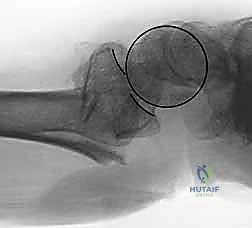

- تشوه مرئي (Deformity): في حالات الانزياح الكبير، قد يبدو الرسغ معوجاً أو منحنياً بشكل غير طبيعي. يُعرف التشوه الكلاسيكي باسم "تشوه شوكة العشاء" (Dinner Fork Deformity)، حيث ينزاح الرسغ للخلف.

- الأشعة السينية (X-rays):

هي الخطوة الأولى لتقييم الكسر. يتم أخذ صور من زوايا متعددة (أمامية خلفية، جانبية، ومائلة) لتحديد موقع الكسر الأساسي ودرجة الانزياح والتقصير في عظم الكعبرة.